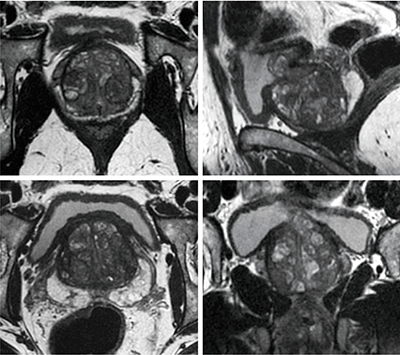

“HyperSense(ハイパーセンス)”は,圧縮センシングとバリアブルkスペースサンプリングを用いたパラレルイメージング法ARCを組み合わせた高速撮像法で,従来のパラレルイメージングのみでは実質的に難しい高いアクセラレーションファクタの臨床応用を可能とする,画期的な高速スキャン技術である。2Dスキャンにおいては前述の動き補正技術“PROPELLER MB”とARCを組み合わせることで,約30〜50%の時間短縮と動き補正を同時に実現可能である。より高速化が必要な3Dスキャンにおいては,圧縮センシングとARCを併用する(HyperSense)ことで,画質劣化を最小限に抑えながら最大50%以上の時間短縮が実現可能であり,実際に導入している施設のほとんどで全身領域において有効活用されている。

また,HyperSenseは,局所撮像技術の“HyperCube”と併用が可能なため,関心領域だけを限定してスキャンすることで,さらなる時間短縮が可能となる。実際に,従来骨盤領域で2Dスキャン3断面を撮像していた施設において,SIGNA Works導入により0.8mmアイソボクセルの3Dスキャンに変更し,空間分解能を上げながら撮像時間を45%短縮したというケース(図4)や,呼吸同期で撮像されていた3D MRCPが,HyperSenseを用いて息止め時間内でも十分診断に値する画像が得られている(図5)など,その有用性が多数報告されている。

図4 圧縮センシングと局所イメージング併用による高速スキャン

(各断面へのリフォーマット像)

(画像ご提供:Tennon Hospital様)